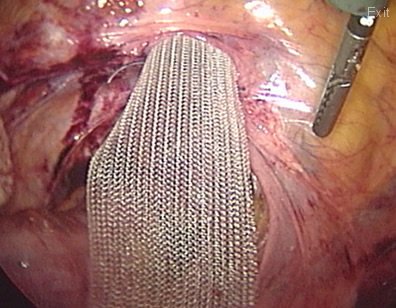

This other patient has a very troublesome prolapse: A vaginal eversion. The vaginal canal is coming "inside out".

In this patient with a vaginal eversion; a mesh is attached to the vaginal vault and the vagina is pulled towards the pelvic cavity. The other end of the mesh will be attached to the sacrum bone (sacrum promontorium) to restore the normal anatomy.